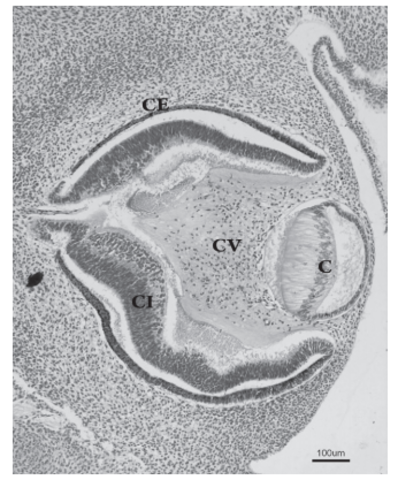

- Durante el día 32 del desarrollo, la placoda cristaliniana se invagina, hasta que un día más tarde se desprende de la superficie ectodérmica, formando la vesícula cristaliniana. Inicialmente ésta presenta una cavidad en su interior. Este fenómeno coincide con la aparición del cuerpo vítreo primario, entre la vesícula y la cúpula óptica.

Las fibras de la pared profunda de la vesícula cristaliniana se diferencian para formar las fibras primarias del cristalino, que se orientan anteroposterormente y son muy transparentes. De esta forma, se va obliterando la cavidad de la vesícula cristaliniana, hecho que ocurre al final de la séptima semana del desarrollo.

- Será ahora la vesícula cristaliniana la que induce la transformación del ectodermo de superficie dando lugar a la córnea, pero en su desarrollo también participarán células de otros orígenes. Así, el epitelio externo corneal es derivado del ectodermo de superficie, además las células derivadas de la cresta neural situadas alrededor de la cúpula óptica emigran y darán lugar al endotelio corneal.

DESARROLLO DEL IRIS Y CUERPO

CILIAR

-El iris se forma a partir del reborde de la cúpula óptica,

cubriendo parcialmente al cristalino. El epitelio iridiano

presenta las dos capas de la cúpula óptica; se continúa con el epitelio del cuerpo ciliar y con el epitelio

retiniano pigmentario y sensorial.